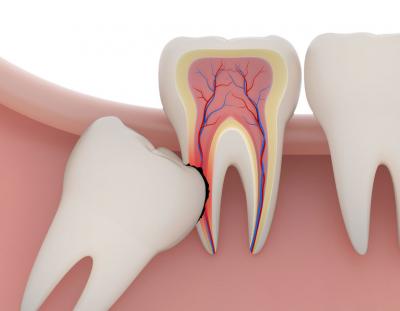

Дистопированный зуб. Занимает неправильное положение и растёт криво или под углом. Он может принимать различное положение: смещаться по оси, упираться в соседний зуб, расти в щеку.

Возможные последствия – неправильный прикус, практическое неучастие в процессе пережёвывания пищи, травмы щеки, языка, воспалённая десна.

Справка. Зуб мудрости зачастую дистопируется по причине позднего прорезывания, – места для правильного расположения зубов в челюсти не хватает, да и зубов, оказывающих поддержку и задающих вектор роста, попросту нет, поэтому частенько они растут с наклоном, мешая вторым молярам.